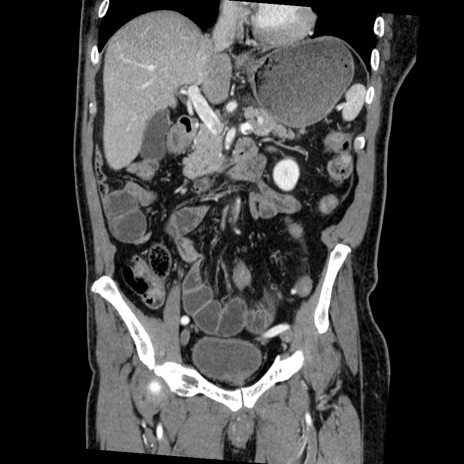

症例22(冠状断像)

【症例】50歳代男性

【主訴】腹痛

【現病歴】AVMからの被殻出血のため回復期リハ病棟入院中。 本日午後3時頃急に下腹部痛が出現した。

【既往歴】AVM、被殻出血、虫垂炎、高血圧

【身体所見】意識晴明、左半身不全麻痺、会話の理解は良好、36.5°C、腹部:膨隆、全体に板状硬、下腹部正中に圧痛点あり、反跳痛-、筋性防御不明、右下腹部にope scar

【データ】WBC 9400、CRP 0.06